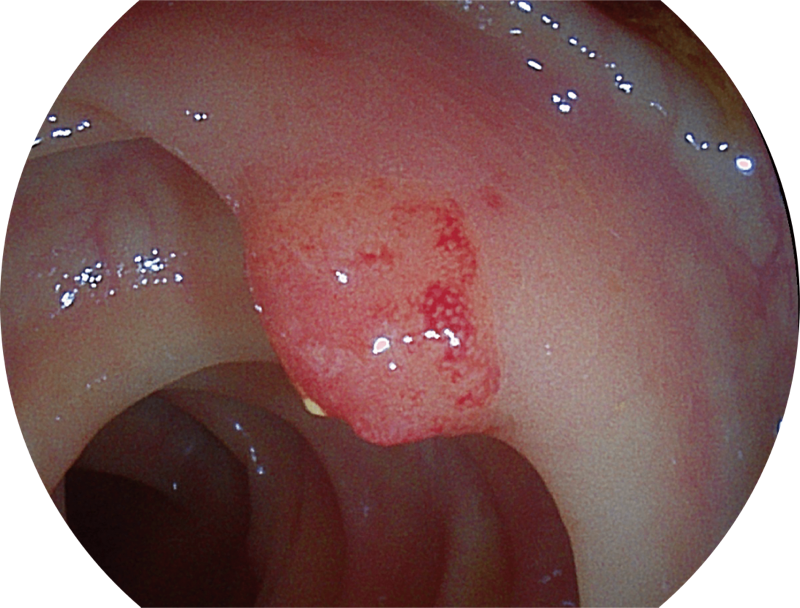

能够凸显黏膜浅层和中层血管轮廓,适用于中、远景观察下的病灶识别和早癌筛查。

(Spectral Focused lmaging, SFI)